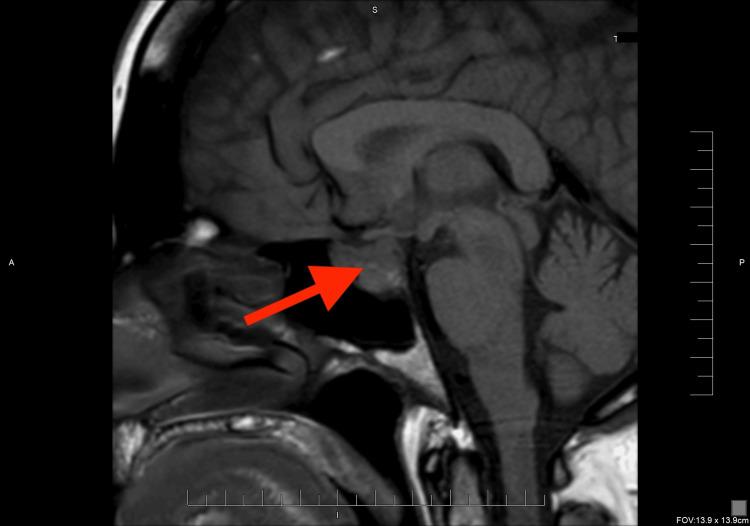

Sex hormones play a crucial role in the development and growth of meningioma. It was observed that meningiomas increase in size and become more symptomatic during pregnancy. Similarly, the use of hormonal therapy, including gonadotropin-releasing hormone (GnRH) agonist, can be associated with an increased risk for meningioma. We reported a 45-year-old woman with a past medical history of hypothyroidism and mild hyperprolactinemia who received hormonal therapy for infertility, including GnRH. She has experienced a persistent headache and left retro-orbital pain with eye movement. Her MRI brain scan revealed a soft tissue mass involving the sellar and left cavernous sinus with a slight impingement of the optic chiasm and left optic nerve, concerning for meningioma or pituitary adenoma. Further laboratory workup showed secondary adrenal insufficiency, which was treated with replacement glucocorticoid therapy. Following tumor resection and histological examination, the diagnosis of sellar meningioma was confirmed. This case report shows a rare association of fertility hormonal treatment with sellar meningioma and how it is challenging to distinguish meningioma from other sellar masses, such as pituitary adenoma, based on clinical presentation and imaging studies.

性激素在脑膜瘤的发生和发展中起着至关重要的作用。据观察,脑膜瘤在孕期体积会增大且症状会加重。同样,使用包括促性腺激素释放激素(GnRH)激动剂在内的激素疗法,可能会增加患脑膜瘤的风险。我们报告了一名45岁女性,她有甲状腺功能减退和轻度高泌乳素血症病史,因不孕症接受了包括GnRH在内的激素治疗。她一直头痛,眼球活动时伴有左眶后疼痛。她的脑部MRI扫描显示鞍区和左侧海绵窦有一软组织肿块,对视交叉和左侧视神经有轻微压迫,怀疑为脑膜瘤或垂体腺瘤。进一步的实验室检查显示继发性肾上腺功能不全,并接受了糖皮质激素替代治疗。肿瘤切除及组织学检查后,确诊为鞍区脑膜瘤。本病例报告显示了生育激素治疗与鞍区脑膜瘤之间罕见的关联,以及基于临床表现和影像学研究将脑膜瘤与其他鞍区肿块(如垂体腺瘤)区分开来具有挑战性。